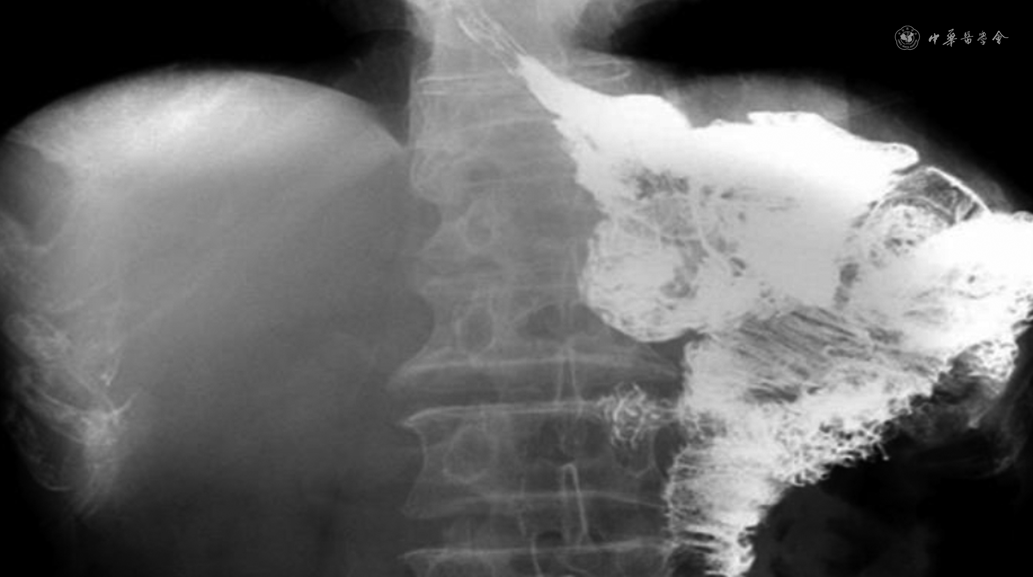

10例患者的临床资料见表1。10例患者均成功实施腹腔镜保留贲门胃癌根治术,无中转开腹,消化道重建时间20~30(24.8±3.3)min,术中出血量20~100(35±24)ml。术后排气时间2~3(2.5±0.9)d,术后进食流质饮食时间2~3(2.25±0.87)d,术后住院时间6~13(9.5±2.1)d。术后未发生出血、吻合口瘘或吻合口狭窄等手术相关并发症,根据外科并发症的Clavien-Dindo分级[7],Ⅰ级1例,无Ⅱ~Ⅴ级并发症。术后病理显示切除标本近远端切缘均阴性,第1组清扫淋巴结2~3枚,有1例患者阳性;第2组清扫淋巴结1~2枚,均阴性。患者术后随访时间分别是2~15个月,中位随访时间6个月,随访期间无死亡或肿瘤复发转移病例。术后患者无反流症状,术后1个月胃肠造影无反流征象(图3),术后2个月血红蛋白、白蛋白、前白蛋白、体质指数和总淋巴细胞计数均恢复至术前水平(表2)。与全胃切除和近端胃切除相比,保留贲门功能胃癌根治术理论上能降低反流性食管炎发生率。采用手工缝合法进行消化道重建,可以减少2~3个吻合器枪钉的应用,降低了手术材料费。